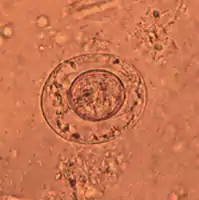

As its name implies (Ancient Greek: νᾶνος, nānos – dwarf), it is a small species, seldom exceeding 40 mm long and 1 mm wide. The scolex bears a retractable rostellum armed with a single circle of 20 to 30 hooks. The scolex also has four suckers, or a tetrad. The neck is long and slender, and the segments are wider than long. Genital pores are unilateral, and each mature segment contains three testes. After apolysis, gravid segments disintegrate, releasing eggs, which measure 30 to 47 µm in diameter. The oncosphere is covered with a thin, hyaline, outer membrane and an inner, thick membrane with polar thickenings that bear several filaments. The heavy embryophores that give taeniid eggs their characteristic striated appearance are lacking in this and the other families of tapeworms infecting humans. The rostellum remains invaginated in the apex of the organ. Rostellar hooklets are shaped like tuning forks. The neck is long and slender, the region of growth. The strobila starts with short, narrow proglottids, followed with mature ones.